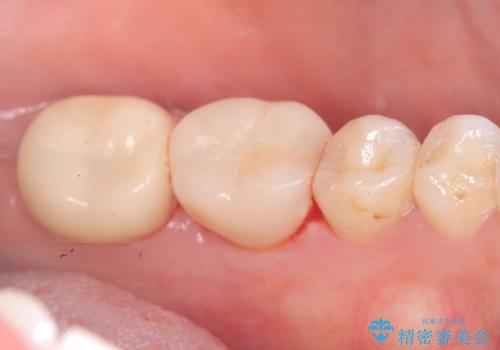

骨との定着を確認し、今後矯正治療を行う予定のためレジン冠をセットしています。